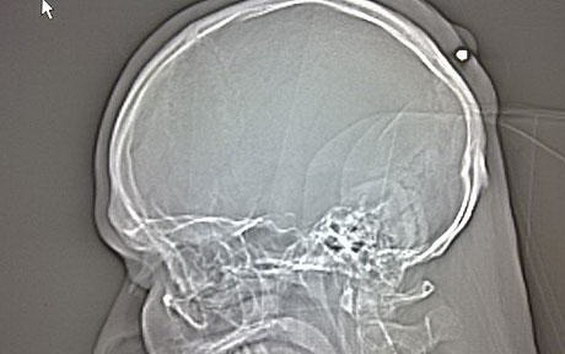

рентген снимкаРентген снимка на која јасно се гледа куршумот

Претставник на полицијата изјавил дека мажот се сеќава дека чувствувал болка во главата, но не побарал медицинска помош. За среќа куршумот не го пробил черепот, а бил откриен дури сега, откако мажот отишол во болница за да му испитаат „грутка“ на главата.

Во петокот куршумот бил изваден со операција и се очекува мажот којшто веќе неколку години живее во Германија да биде пуштен од болница во текот на оваа седмица.